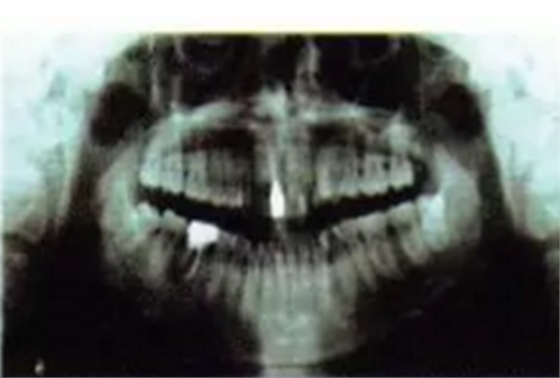

曲面全景片可見1為樁核冠、根尖1/3欠充,但未見陰影。1根方見多生牙高密度影。6遠(yuǎn)中根外吸收、根管欠充,根尖周圍可見透射陰影,牙周膜增寬。上前牙及63近遠(yuǎn)中牙槽骨度輕度水平吸收。1牙根尖片見其牙周膜清晰度尚可,未見根骨粘連。頭顱側(cè)位片測量結(jié)果示患者為I類、均角骨面型,上前牙和下前牙唇傾度減?。▓D3)。

圖3術(shù)前曲面全景片